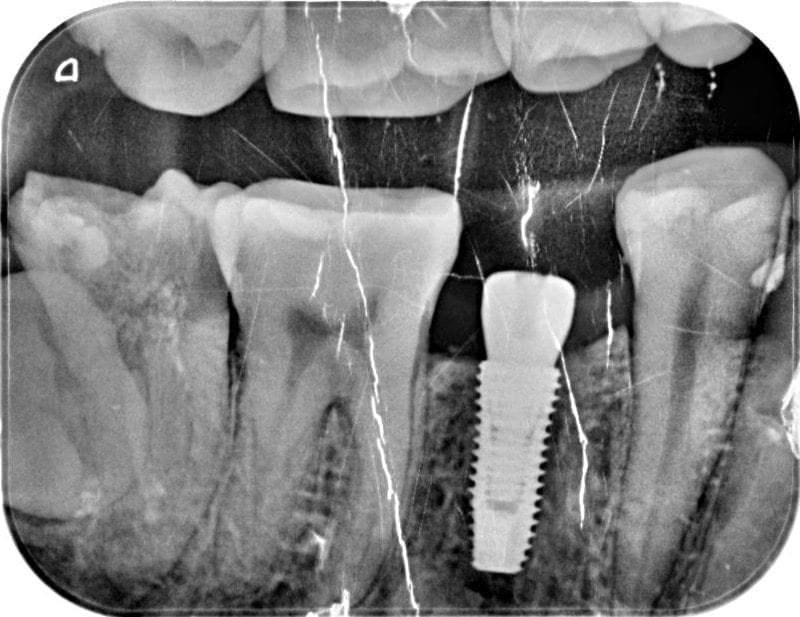

圖示:初步看診時Mr.Su主訴不適位置的X光照,右下第二小臼齒根管治療未修復而導致牙齒斷裂

疼痛的右下第二小臼齒,早年根管治療後因未做完整的修復,牙齒發生斷裂情況;且牙齒的結構不足,導致無法保留,因此建議牙齒拔除。

圖示:植牙手術後的X光照,植體穩定度良好

圖示:安裝人工植牙假牙前後的X光照